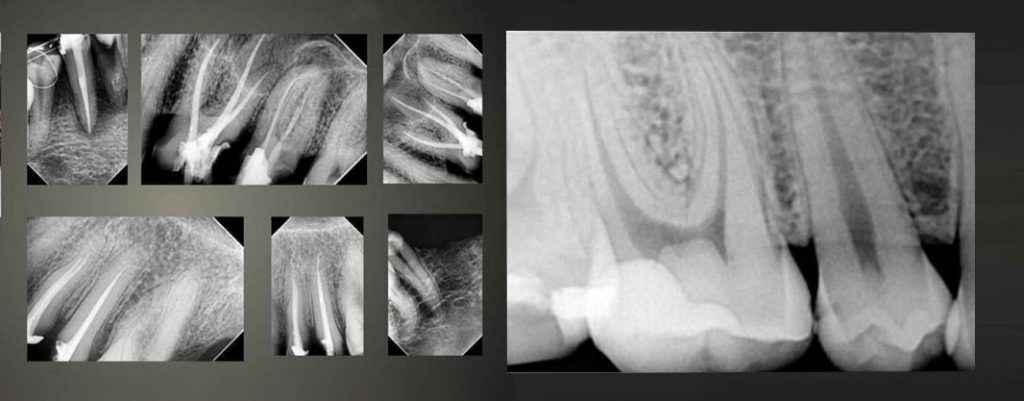

Thinnest sensor (4.4mm) as compared to all others available, ergonomic design, dust-proof and water-proof. Excellent imaging resolution (25lp/mm theoretical resolution), C Mos technology, H1 & H2 sensor types and high flexibility of its cable puts this device in an absolute win-win situation. All its edges are curved to provide maximum comfort to the patient and avoid any accidental injuries. Its reliability and durability increase clinical productivity and a pleasant experience to the patients.

Entire imaging process is so fast that it can be done within 3 seconds. Its smart software is user-friendly and quality of any radiographic image can be improved with just one click. Woodpecker also offers free timely upgrades in the software. Images can be processed as per requirement via simple tolls in the software. Another astonishing feature is that more than one computer can be connected to the software license.